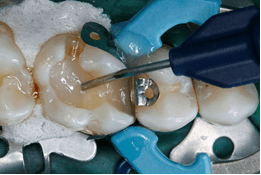

Afb. 4: Volume-opbouw van de dentine met een 4 mm dikke laag met het vloeibare Bulk-Fill-ormocer Admira Fusion x-base.

Afb. 5: Lichtpolymerisatie van het vullingmateriaal gedurende 20 s.

Afb. 6: De goede floweigenschappen garanderen een belletjesvrije bekleding van de caviteitbodem met het laagviskeuze materiaal